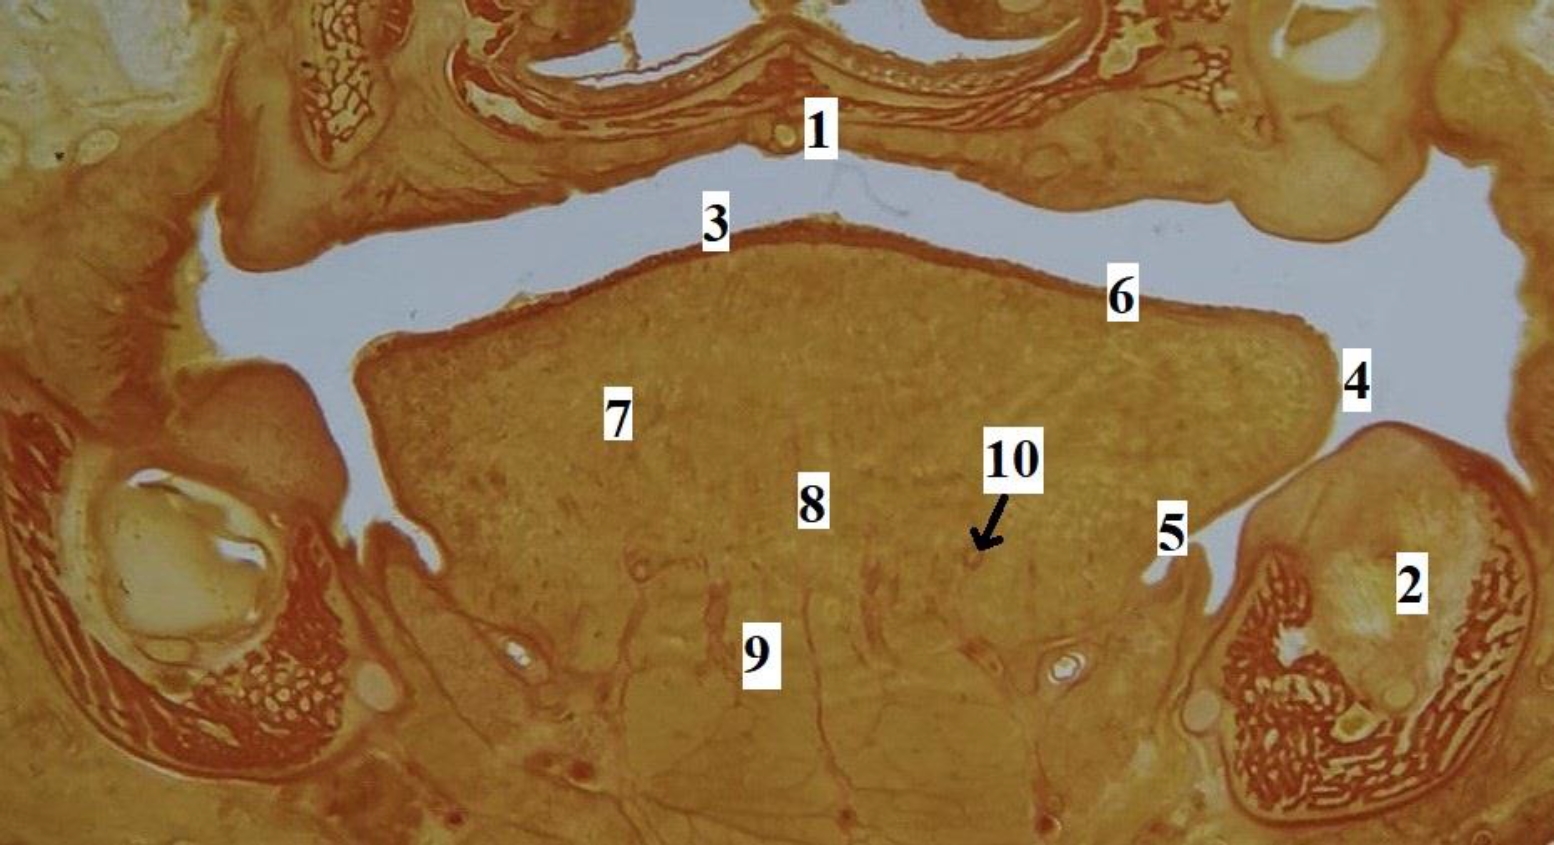

Рис. 3. Язык плода человека. Фронтальная гистотопограмма. Фото под микроскопом MicroOptix MX-1150, ок. ×10, об. 1. Возраст – 22 недели, пол мужской. Окраска по Ван – Гизону: 1 – твердое нёбо; 2 – нижняя челюсть; 3 – спинка языка; 4 – край языка; 5 – эпителий слизистой оболочки нижней поверхности языка; 6 – специализированный эпителий спинки языка; 7 – мышечные волокна поперечной мышцы языка; 8 – перегородка языка; 9 – мышечные волокна подбородочно-язычной мышцы; 10 – глубокая артерия языка